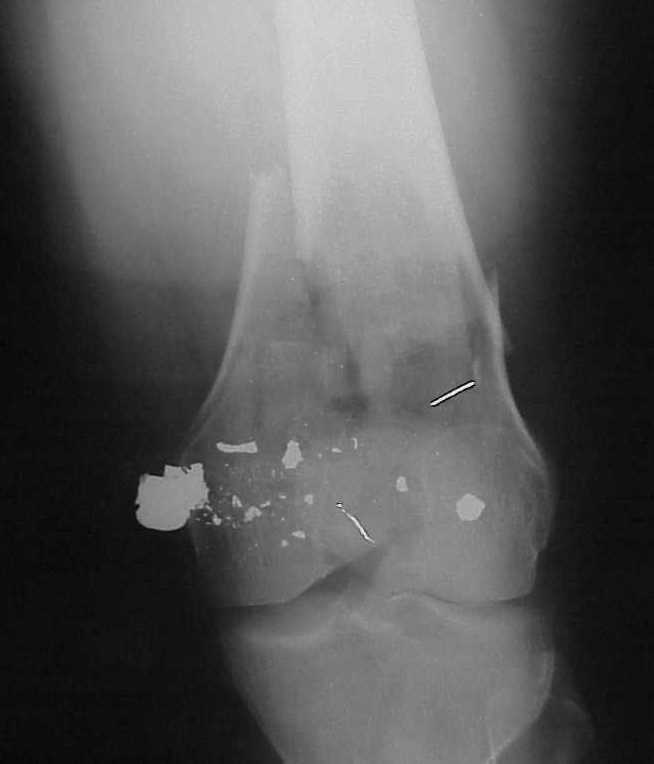

A CT and knee xrays would help identify lateral condyle comminution and/or a "hoffa fragment" of the posterior condyle. I am concerned that the lateral cortex is not sufficient to give purchase for a retrograde IMN. blocking screws could improve this as a possibility. A long blade or LISS if avaible would be my secondary choices. Good luck. Any chance you can get these cases transferred earlier when it

Lateral condyle looks too small for the blade, and the plate too short.

See attached case that was done several years ago before LISS. He had comminuted trochlea and anterior blocking screws were used to prevent anterior IMN cut-out.